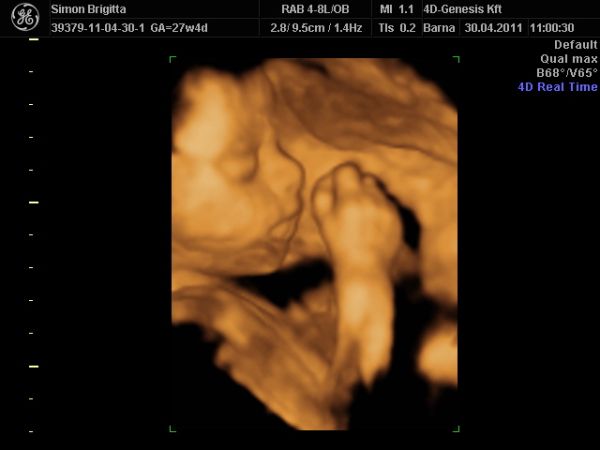

Már nagyon fáradt vagyok, de mindenképpen be akartam jelentkezni, mert ma voltunk a 4D Genesisbe és az étteremben is.

Először természetesen az ultrahangról: annyira szuper volt újra látni a kiscsajt, merthogy még mindig puncis szerencsére :lol:

Most készített a szonográfus 2D-ben néhány igazi "hamburger" fotót!

Teljesen egészséges, fejvégű, mindene rendben van, a méhlepény még mindig mélyen tapad, magzatvíz átlagos, lepény 0. fokban érett.

És legnagyobb meglepetésemre nagyobb a "koránál", a buksija alapján 29+1, az adatok átlaga alapján 28+5 (ténylegesen pedig 27+4).

Becsült súlya 1220 gramm!

Ami a legnagyobb élmény volt nekünk: egy az egyben úgy néz ki, mint Luca a 32. heti 4d-s ultrahangon anno! Hihetetlenül hasonlítanak egymásra!